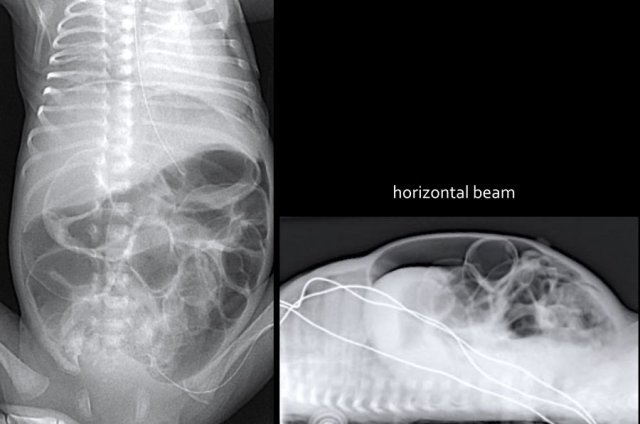

The images show a typical case of NEC with pneumatosis intestinalis.

On the horizontal beam image there is no sign of free air.

The findings are:

- Multiple dilated small bowel loops

- Pneumatosis intestinalis.

- Pneumoperitoneum.

Diagnosis:

NEC with perforation.